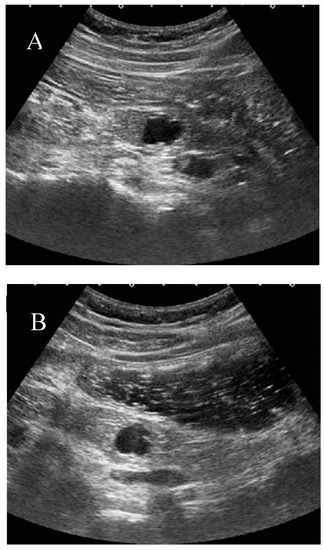

At our institution, the liquid-filled stomach method with Fowler’s position is usually added after conventional screening of the pancreas. This method, in particular, improves the visualization of the pancreatic body and tail by eliminating gastric gas. (Figure 3) This method also helps visualize the pancreatic uncinate and ampulla by enhancing the contrast between the target and intestine.

Figure 3. The liquid-filled stomach method. The pancreas tail is not well visualized due to gastric gas in normal examination (A). However, the pancreatic body to tail become clearly visualized after intake of milk tea with Fowler’s position (B).